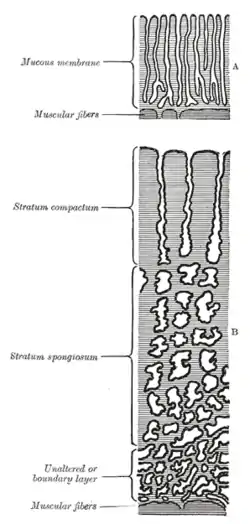

Diagrammatic sections of the uterine mucous membrane: A. The non-pregnant uterus. B. Decidua parietalis; the mucous membrane in the pregnant uterus and not beneath the placenta. | |

The part of the decidua that interacts with the trophoblast is the decidua basalis (also called decidua placentalis), while the decidua capsularis grows over the embryo on the luminal side, enclosing it into the endometrium. The remainder of the decidua is termed the decidua parietalis or decidua vera, and it will fuse with the decidua capsularis by the fourth month of gestation.

Three morphologically distinct layers of the decidua basalis can then be described:

- Compact outer layer (stratum compactum)

- Intermediate layer (stratum spongiosum)

- Boundary layer adjacent to the myometrium (stratum basalis)